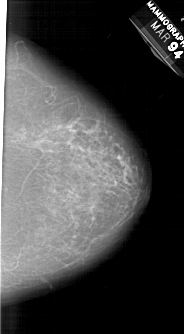

A_1300_1.RIGHT_MLO

RIGHT_MLO LINES 6691 PIXELS_PER_LINE 4111 BITS_PER_PIXEL 12 RESOLUTION 43.5 NON_OVERLAY